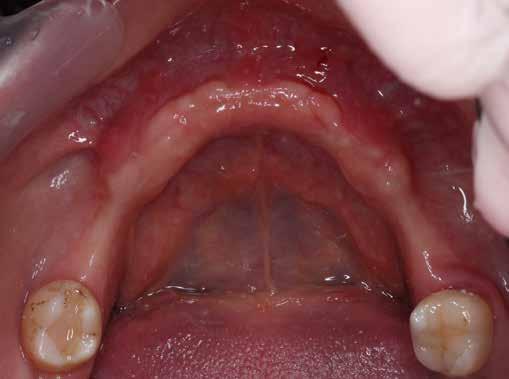

A 68 éves nőpáciens, panaszt (fájdalom, ráharapási érzékenység) okozó bal oldali felső, első kisőrlő foga miatt jelentkezett rendelőnkben. Az általános anamnézisben említést érdemlő betegség, műtét nem szerepel. Az elvégzett klinikai és radiológiai vizsgálatok (1., 2. ábra) endo-parodontális érintettséget igazoltak, vertikális fraktúra gyanújával. A fog harmadfokban mozgatható volt, a bukkális oldalon 14 mm-es tapadásveszteséggel. A reménytelen parodontális prognózis a fog eltávolításának abszolút indikációját jelentette. Hídpótlás készítéséhez a szemfog előkészítése lett volna szükséges, illetve csak vegyesen rögzített (implantátum-fog) hídpótlás készítése lett volna lehetséges. Figyelembe véve a szemfog anyagának védelmét, parodontális állapotát (a szemfognál is észlelhető volt tapadásveszteség, noha a fog stabil volt) és azt a tényt, hogy a szakirodalomban nem találtunk egyértelmű ajánlást vagy vizsgálatot, amely megbízhatóan alátámasztaná az ilyen státuszban fogon és implantátumon vegyesen rögzített protetikai megoldás hosszú távú megfelelőségét, a preoperatív konzultáció során, a pácienssel egyeztetve a hídpótlás készítését elvetettük, és implantációs fogpótlás készítése mellett döntöttünk. A protetikai szemléletű,

„visszafelé” tervezés elveit követtük a hosszú távú funkcionális, esztétikai siker és szöveti stabilitás elérése érdekében. Ezek alappillére az implantátum megfelelő pozicionálása, amelyre akkor nyílik lehetőségünk, ha a fog eltávolítását követően megfelelő mennyiségű és minőségű csontkínálattal rendelkezünk. A páciens kivizsgálása és megfelelő előkészítése után, a fog eltávolításával egy időben PRF Stikcy Bone™ segítségével kivitelezett alveólus prezerváció mellett döntöttünk, a megfelelő mennyiségű és minőségű csontos és mukogingivális gyógyulás elősegítése érdekében. A PRF készítmény mennyiségét, minőségét, kezelhetőségét és hatékonyságát jelentősen befolyásolják a páciens laborértékei, ezért a PRF csont augmentáció esetén, a műtétet megelőzően mindig laborvizsgálatot végzünk (hemoglobin: 134 g/liter, hematokrit: 0,43, fehérvérsejt: 6,6 G/ liter, CRP: 3,60 mg/liter, vércukor: 5,2 mmol/liter, összkoleszterin: 7,00 mmol/liter, triglicerid: 1,28 mmol/liter, HDL koleszterin: 1,02 mmol/liter, LDL koleszterin: 4,8 mmol/ liter), D3-vitamin: 117,5 nmol/liter).

A foggyökér óvatos, atraumatikus eltávolítását követően excochleáltuk a parodontális és periapikális gyulladásos folyamatok eredményeként jelen lévő sarjszövetet. Az alapos tisztítás és a bukkális csontfal hiánya miatt indokolt membrántechnika megfelelő kivitelezése céljából mukoperioszteális lebenyt képeztünk, a lebeny tervezésénél arra törekedtünk, hogy az a lehető legkisebb méretű legyen és a második kisőrlő fog helyén lévő implantátum hámtapadását ne érintse, illetve, hogy lehetővé tegye a szemfog parodontális kezelését is (3., 4. ábra). Az alveoláris csont megőrzésének és regenerációjának segítése céljából a fog eltávolításával egy időben alveólus prezervációt végeztünk Stikcy Bone™ és PRF membránok segítségével, melyek előállításánál követtük a J. Choukroun által megadott vérvételi és centrifugálási protokollt (20). Kizárólag Process for PRF Duo Quattro System eszközöket, centrifugát, vérvételi egységet és csöveket, a membránok előállításához PRF Box-ot használtunk. Az A-PRF és S-PRF csöveket a PomPac eljárásnak megfelelően 4 °C-ra előhűtöttük. A Stikcy Bone™ készítmény előállításához Purgo™ xenografot használtunk. Az alveolust a grafttal feltöltöttük, tömörítő műszerrel enyhe kompreszsziót, illetve vertikális irányban 10 százaléknyi túlkompen-

zációt alkalmaztunk (5., 6. ábra). Ezt követően a palatinális marginális gingivát óvatosan alápreparálva a bukkális defektust, valamint az okkluzális felszínt keresztirányban A-PRF membránokkal borítottuk (7. ábra). A mukogingivális lebenyt – annak megnyújtása nélkül – a helyére fektettük és varratokkal rögzítettük, per primam sebzárást nem végeztünk (8., 9. ábra). A varratokat 2 hét után távolítottuk el, a varratszedésig a sebgyógyulás támogatására per os 1000 mg/nap C- és 12 000 NE/nap D-vitamint adtunk (20). A műtéti beavatkozást 24 hét gyógyulási időszak követte, melynek során sem helyi, sem gyógyszeres kezelés nem történt, az esztétikum javítása érdekében a páciens ideiglenes kivehető fogpótlást használt. A csontos gyógyulás ellenőrzése és az implantáció tervezése céljából állcsonti CT felvételt készítettünk, illetve lenyomatvételt végeztünk. A CT felvételen tökéletes csontos gyógyulást észleltünk, az alveolaris csont volumene teljes mértékben megtartott volt (10. ábra), a klinikai kép is ennek megfelelően alakult (11., 12. ábra) A Trishape Implant Studio™ a korábbi csont augmentáció területén, a felső állcsontnál áltagosnak számító D2-D3 csontminőséget jelzett (13. ábra). A lenyomat alapján készített gipszmodellt szkennelve virtuális mintát nyertünk. A CBCT felvétel és a virtuális modell adatait a Dual Scan protokoll (21) elveinek megfelelően használtuk fel az implantációs sablon (New Age Dental Kft, Nemeskéry Károly) készítéséhez (14., 15., 16. ábra). Az implantátum (Ankylos C/X A11) behelyezése teljesen navigált módon, 35 Ncm primer stabilitással történt (17., 18. ábra). Az implantátumra a fogtechnikus (D1 Dental Kft., Garamvári Csaba) által előzetesen elkészített csavarozott, ideiglenes fogpótlást rögzítettünk a gyártó által előírt 15 Ncm-es nyomatékkal, az ideiglenes korona az okklúzióban és artikulációban nem vett részt (19., 20., 21. ábra). A front- és prémoláris régióban, amennyiben lehetséges, mindig nyílt gyógyulási protokollt választunk, azonnali ideiglenes restaurátumot készítve, így biztosítva elegendő időt a lágyrészek maturációjához (23, 24, 25, 26, 27). A kontrollvizsgálatok során havonta ellenőriztük az ideiglenes fogpótlás és az implantátum stabilitását, valamint a lágyrészek állapotát, korrekciós beavatkozás vagy az ideiglenes korona emergencia-profiljának változtatása nem volt szükséges (22. ábra). Két hónapos terhelésmentes időszakot követően, csont-tréninget alkalmaztunk részleges terheléssel, a teljes terhelést a hatodik hónap végére értük el, és megkezdtük a definitív protetikai ellátást. Az ideiglenes restaurátum eltávolításakor az alveoláris struktúrák tökéletes gyógyulását észleltük, a páciens ínye békés, reakciómentes volt, megfelelő mennyiségű keratinizált, feszes ínnyel rendelkezett (23. ábra). Az implantátum stabilitása Periotest-tel -8 értékű volt. Cerec Omnicam rendszerrel digitális lenyomatot vettünk (24. ábra), és a fogtechnikus (Prodont Silver Kft., Panyi János) által ragasztott, csavarozott hibridkerámia koronát készíttettünk nem indexált Ankylos C/ titanium-base fej felhasználásával, amelyet az előírás szerinti 15 Ncm-es nyomatékkal rögzítettünk (25., 26 ábra), majd ellenőriztük az okklúziót és az artikulációt (27. ábra). A beavatkozást követően 6 hónappal az alveoláris struktúrák stabilak, a röntgenfelvételen a csontállomány megtartott, a beteg panaszmentes, rágó funkciója kifogástalan, az esztétikai eredménnyel teljes mértékben elégedett (28., 29., 30. ábra)